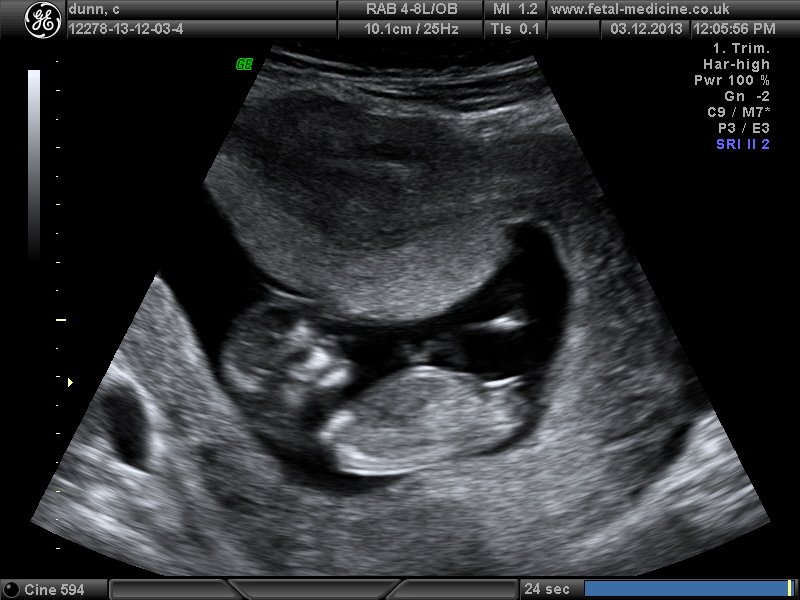

hello, please have a guess boy or girl, thankyou scan was 12+1 day.